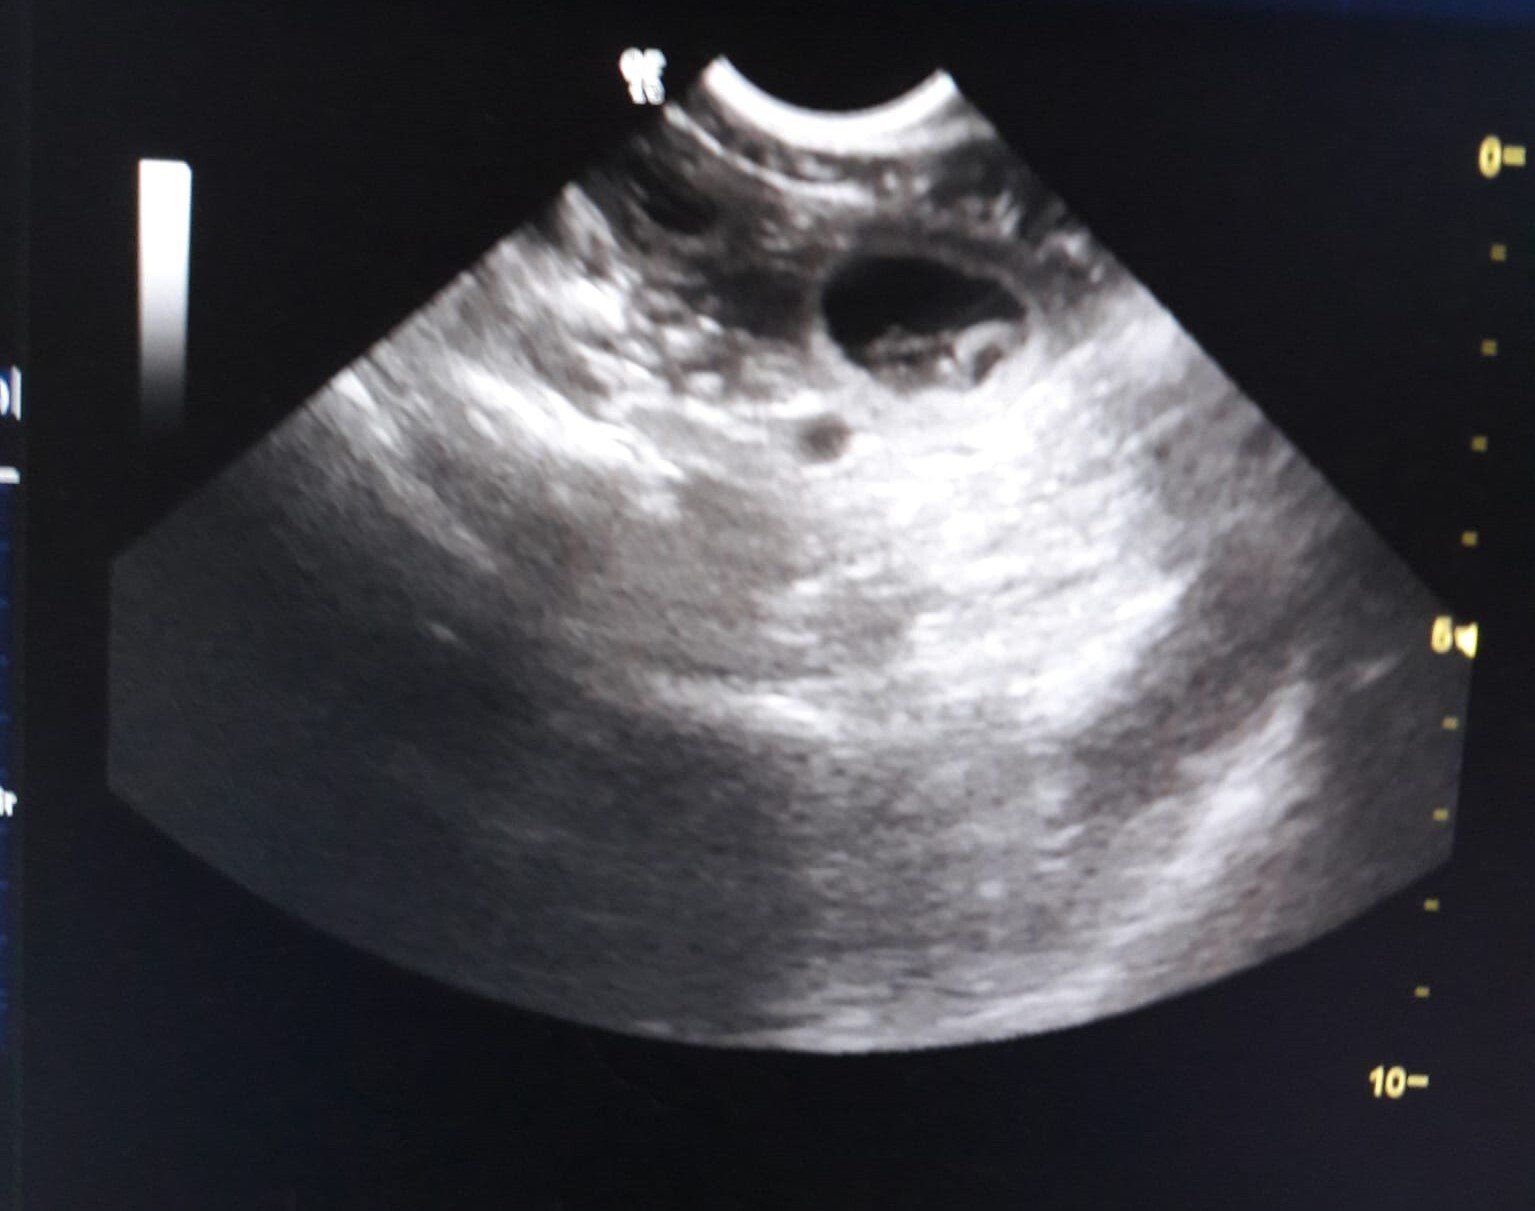

Die heutige Ultraschall Untersuchung ergab das unsere Bones tragend ist.

Wir erwarten somit Anfang Mai unseren E-Wurf.